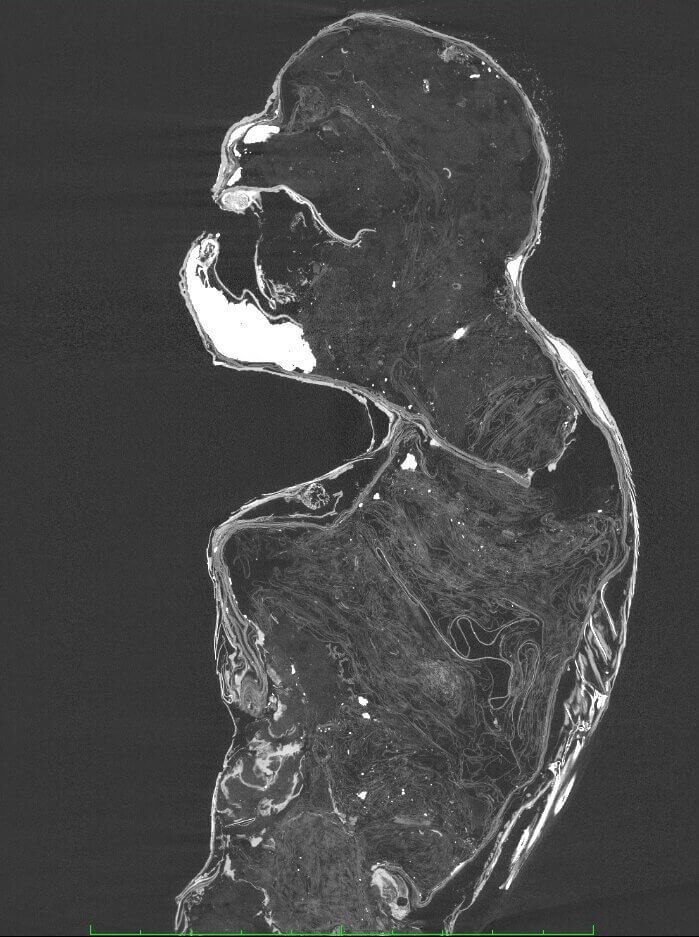

調查結果顯示,有關上半部的「人身」,從斷層掃瞄的影像可看出並沒有像是頭骨、背骨等主要骨骼,其內部由綿進行填充。

「人魚木乃伊」從斷層掃瞄的影像可看出並沒有像是頭骨、背骨等主要骨骼。圖/取自倉敷藝術科學大學網頁kusa.ac.jp看起來像猴子的外觀,則是用上了紙和布,並在表面塗上混合砂及炭的塗料。而像孟克作品「吶喊」神情的臉,大部分都是用紙等物品製作。牙齒使用的是肉食魚類的牙齒,身體表面也被貼上河豚皮及動物毛髮。